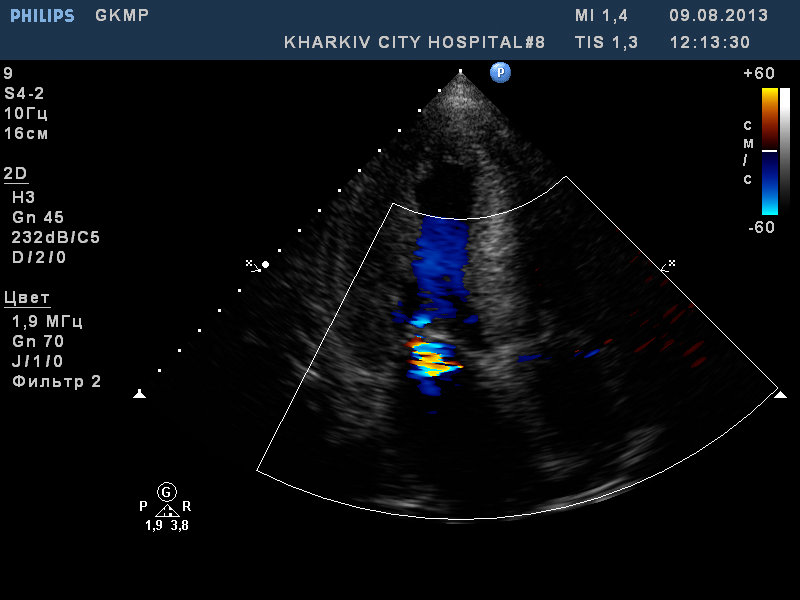

ГКМП. обструкции кровотока в выносящем тракте левого желудочка нет.